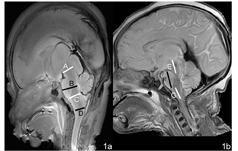

在3.0T与7.0T标本MRI上获取脑干生物学数据,应用eFilm软件进行测量,精确度为0.1 mm。所有数据由3位影像学工作者同时测量每个部位,测量2次,取平均值。具体测量项目及方法如下(图1):选取通过中脑导水管全长和第四脑室入小脑延髓池中孔全长平面作为正中矢状面,以此正中矢状面作为测量平面,在此平面上测量脑干各径线长度。脑干前后经,采用4条径线表示:A线,大脑脚前缘中点与中脑水管中点间距离;B线,脑桥前缘中点与第四脑室底最短距离;C线,脑桥与延髓移行部的最短距离;D线,延髓与脊髓移行部的最短距离。脑干长径采用3条径线表示:E线,大脑脚长轴距离;F线,脑桥长轴距离;G线,延髓长轴距离。在本研究中没考虑侧别与性别因素。

脑干正中矢状面各径线的测量值随胎龄增长的变化见图2。脑干正中矢状面各径线测量值数据随着胎龄增长成线性增加。由于直线的斜率不同,可见脑干内部各结构是以不同的速度增长的。F线(斜率为0.0494)增长是最快,C线(斜率为0.0319)与G(斜率为0.0330)线增长速度居中,D线(斜率为0.0176)增长是最慢;A线(斜率为0.0279)和E线(斜率为0.0268)几乎保持同样速度增长;B线(斜率为0.0469)和F线也几乎保持同样速度增长。置信区间见表2。